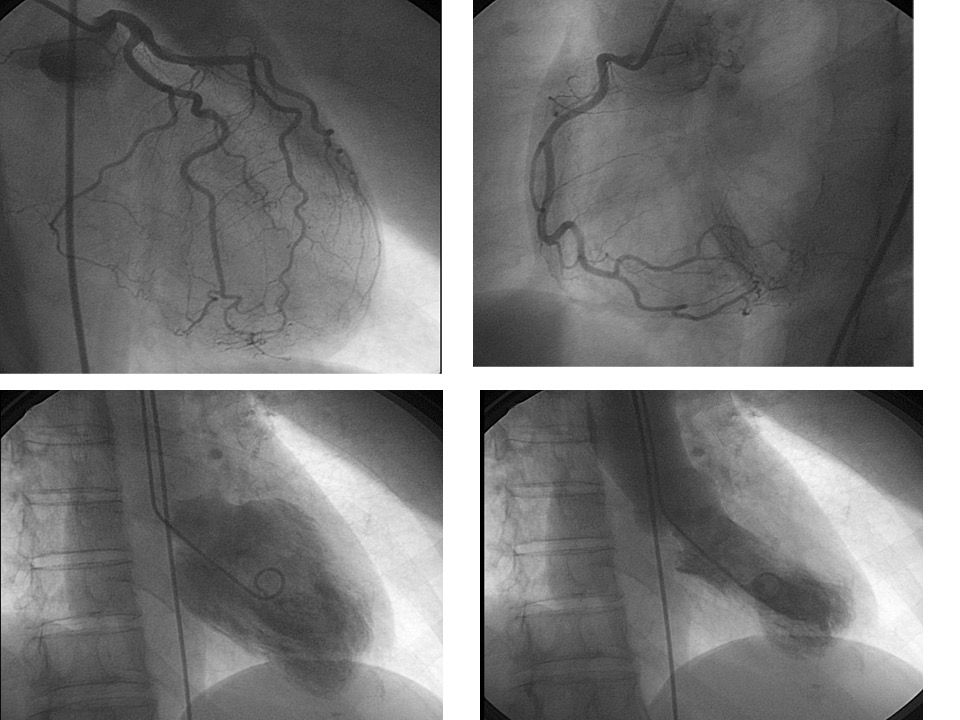

Foto e video